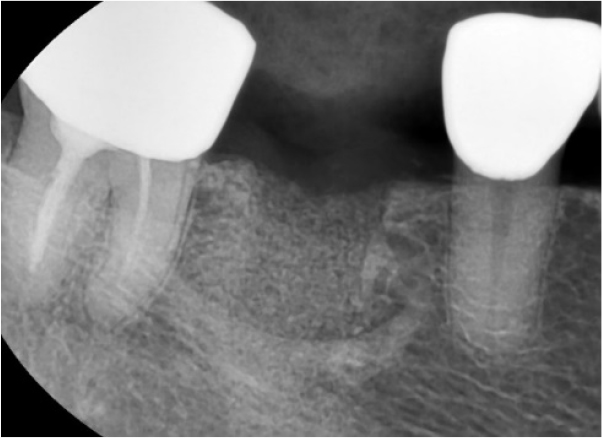

There was slightly sloughing tissue in the open healing area one month later, the healing of the socket seemed like a crater pattern. However, after 4 months, high-quality keratinized mucosa was secured (Figs. 7, 8, and 9). At the time of flap opening for implant placement, the bone was maintained at the ideal height and width. The bone quality was sufficient to get initial stability (Fig. 10).

An implant of 5.0 mm diameter and 10.0 mm length (Luna®; Shinhung, Seoul, Korea) was placed at the lower right 1st molar site, and the implant stability quotient (ISQ) was 81. The Φ6.0 × 5.0 mm healing abutment was placed and sutured with 4-0 Supramid® (Assut Medical Sarl, Pully-Lausanne, Switzerland) (Fig. 11). It showed stability on the post-operative panoramic radiograph (Fig. 12). After 4 months, the final prosthesis was completed (Figs. 13 and 14).